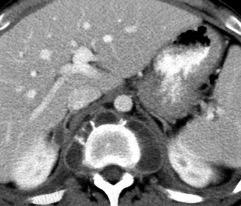

121. MASA MEDIASTÍNICA QUE SE REALZA CON EL CONTRASTE

Metástasis/Paraganglioma

Hematopoyesis extramedular

Basado en: Gurney JW. Contrast-enhancing Mass..en Sten. Gurney. Expertdd/Chest.Amirsys.2011